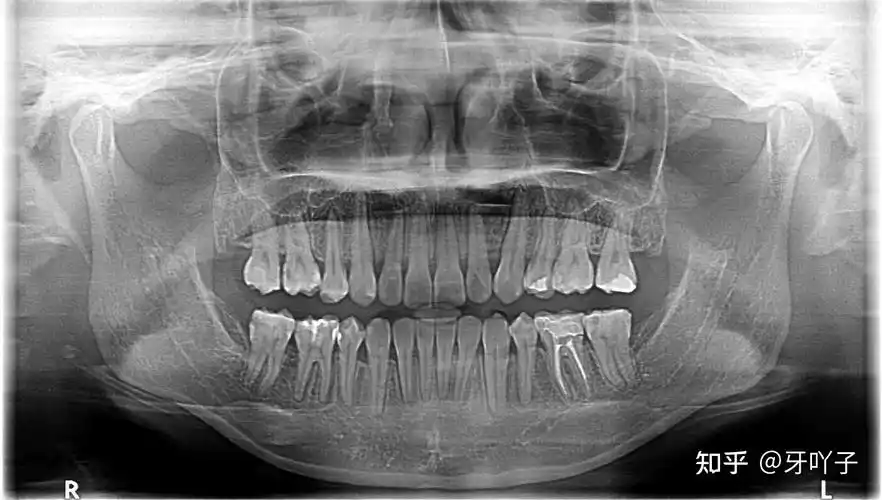

看牙拍片子真的很必要

牙齿医生进,牙齿x片

项目 补牙 恢复时间 0天 收藏 建议大家有时间去给自己牙齿拍个牙片